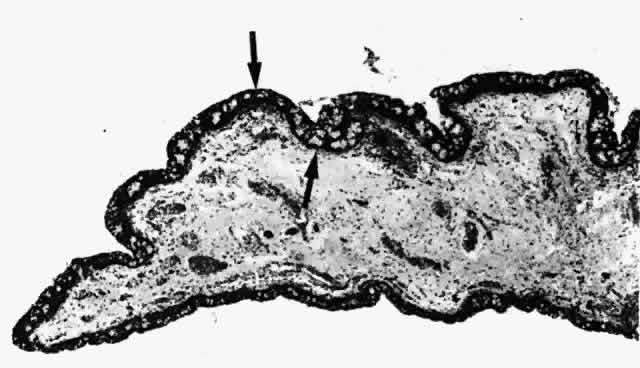

Fig. 7. A. Inferior fornix showing papillary projection (P). B. Inferior fornix demonstrating Krause's glands (KG). (A, × 40; B, × 80)